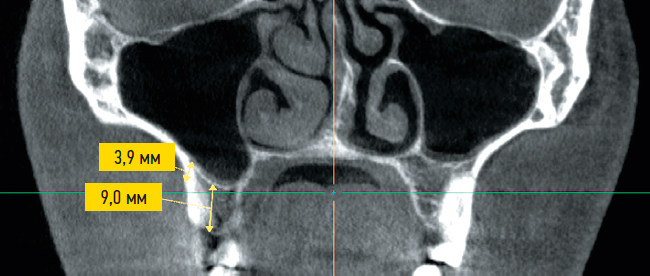

Рис. 2. Корональный срез томограммы: расчет высоты альвеолярного отростка и межкомпактного слоя.

Fig. 2. Coronal section of tomogram: calculation of the alveolar height and intercompact layer.

- высота альвеолярного отростка (области А и Б) (рис. 2);

- расстояние между компактными пластинками дна верхнечелюстной пазухи и альвеолярного отростка подскуловой области (области А и Б) (см. рис. 2);

В анализируемой выборке среднее значение высоты альвеолярного отростка в областях А и Б имели статистически значимые отличия. Средняя высота в области А составила 10,44±2,59 мм, в области Б — 9,53±2,55 мм. Такие различия предположительно связаны с анатомией строения дна гайморовой пазухи.

Среднее расстояние между компактной пластинкой альвеолярного отростка верхней челюсти и компактной пластинкой нижней стенки верхнечелюстной пазухи в области А составило 2,67±0,83 мм, в области Б — 2,46±0,85 мм (различия статистически незначимые). Эти характеристики определяют длину резьбы предполагаемого микроимплантата и его стабильность в костной ткани.